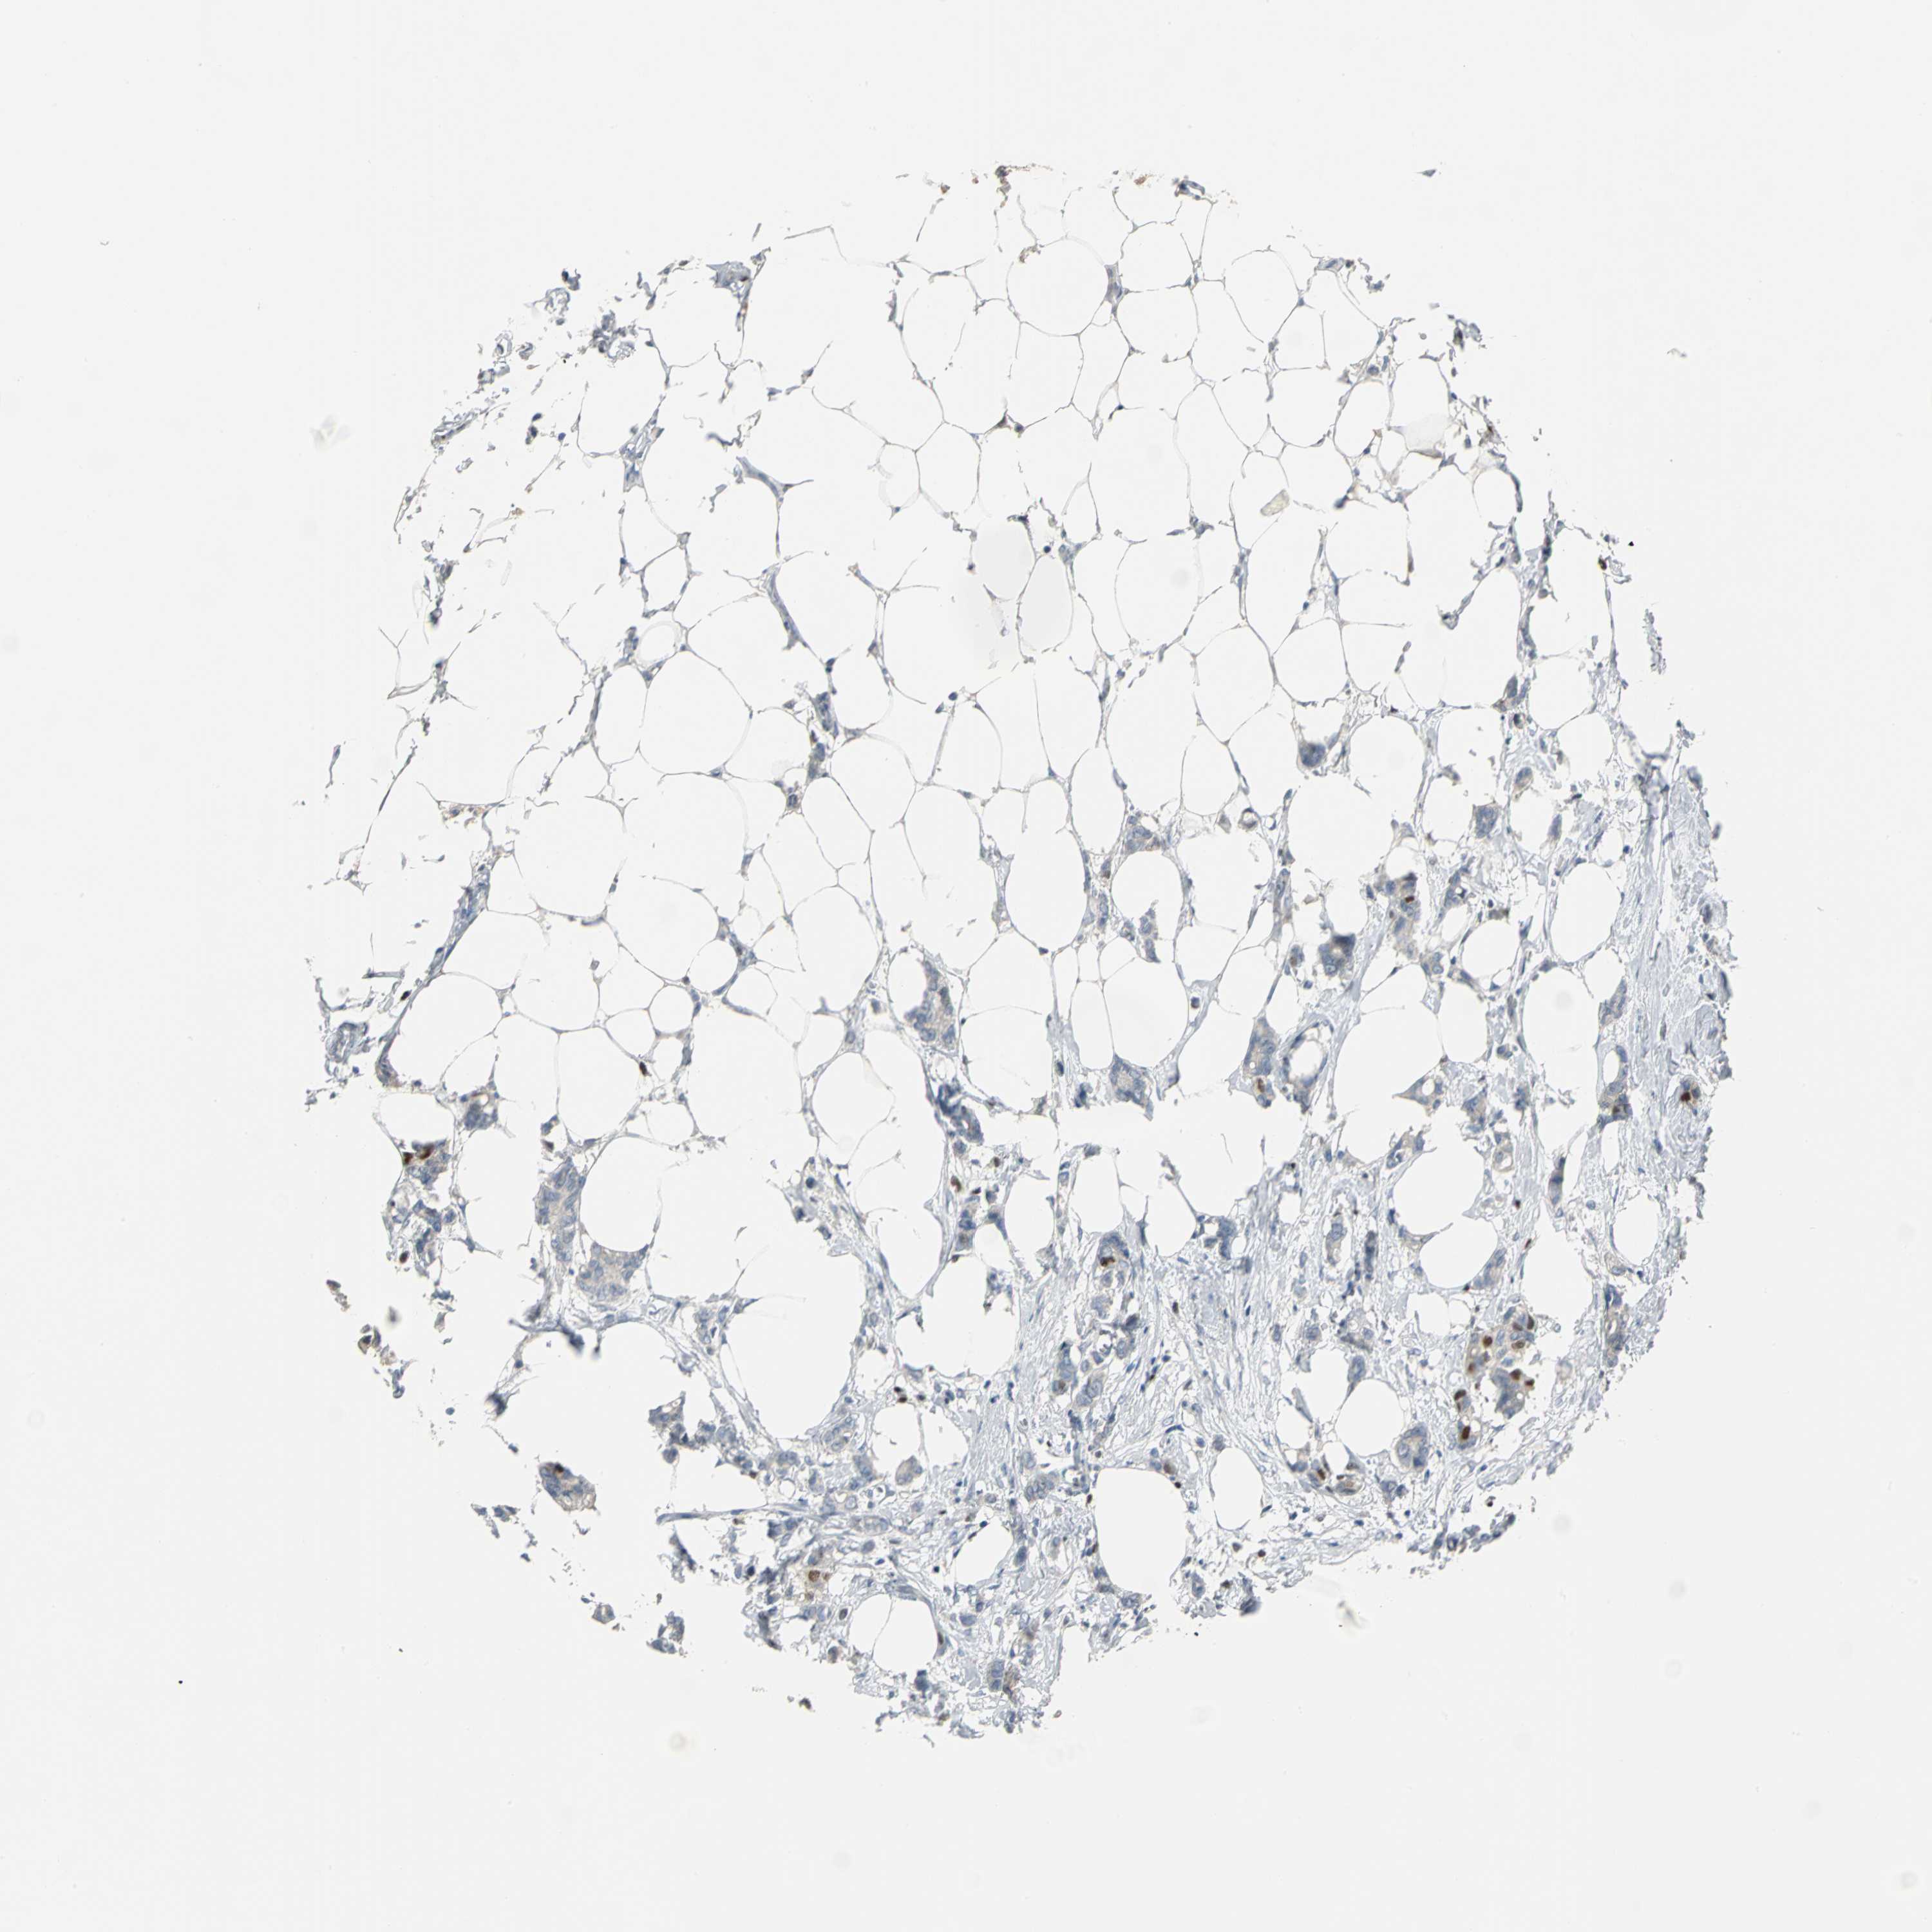

BRCA TCGA BRCA VALIDATION PROTEIN EXPRESSION